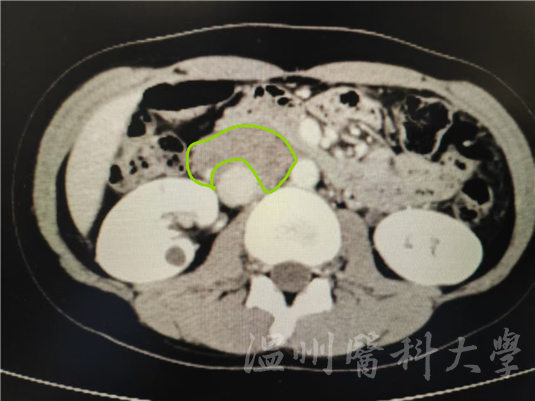

张女士的下腔静脉

这个肿物长得十分“刁钻”,呈“C”形紧紧包绕着下腔静脉,环绕血管管腔约270°,就像藤蔓死死缠住树干,只留下1/4的“安全通道”。正是它压迫周围组织,才导致张女士十年反复腰痛。